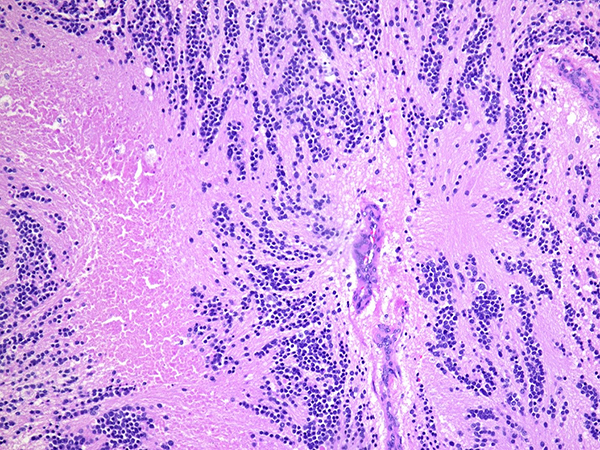

Fig 2. H&E stained section reveals small blue cell tumor amidst eosinophilic fibrillary matrix (20x)

Fig 3. Small blue cells amidst neuropil-rich stroma and foci with comedo-like necrosis (100x)

Fig 4. H&E stained section to highlight small round to oval blue cells with adjacent neuropils and focus of comedo-like necrosis (400x)

Fig 5. Mitotic figures and karyorrhectic debris was noted (400x)

Fig 6. Tumor cells involved thymic parenchyma and adjacent adipose tissues (100x)